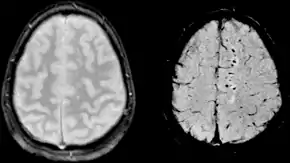

| Sårbarhedsvægtet bilede (SWI) af diffus axonal skade ved et traume med 1,5 teslaer (højre) | |